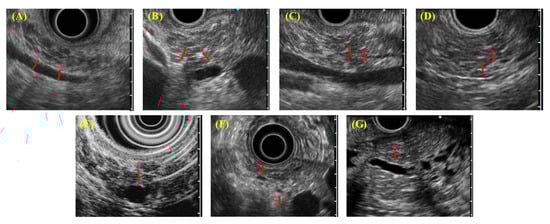

EUS diagnostic findings (Figure 2) include (A) lobularity with honeycombing, (B) lobularity without honeycombing, (C) hyperechoic foci without shadowing, (D) stranding, (E) cysts, (F) dilated side branches, and (G) hyperechoic MPD margins. ECP is diagnosed by imaging when two or more findings, including any feature listed from (A) to (D), are observed. In addition, irregular dilatation in three or more branched pancreatic ducts, as seen by endoscopic retrograde cholangiopancreatography (ERCP), also served as imaging findings for ECP.

Figure 2. Each endoscopic ultrasound (EUS) finding in diagnostic criteria for early chronic pancreatitis 2009 (DCECP2009). (A) Lobularity with honeycombing; (B) lobularity without honeycombing; (C) hyperechoic foci without shadowing; (D) stranding; (E) cysts; (F) dilated side branches; (G) hyperechoic main pancreatic duct (MPD) margins.